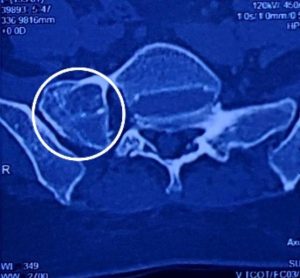

বার্টোলোটি সিন্ড্রোম (Bertolotti Syndrome)

বার্টোলোটি সিন্ড্রোম (Bertolotti Syndrome) হল মেরুদণ্ডের একটি জন্মগত অবস্থা যা পিঠের নিচের অংশে ব্যথা সৃষ্টি করে। এটি এমন একটি অবস্থা যেখানে মেরুদণ্ডের সবচেয়ে নিচের অংশের কশেরুকা (L5) sacrum বা ইলিয়াম (ilium) এর সাথে অস্বাভাবিকভাবে যুক্ত হয়ে যায়। এই অস্বাভাবিক সংযোগের ফলে মেরুদণ্ডের স্বাভাবিক কার্যকারিতা ব্যাহত হয় এবং ব্যথার সৃষ্টি হয়।

বার্টোলোটি সিন্ড্রোম একটি জন্মগত ত্রুটি। এর মূল কারণ হল লাম্বোস্যাক্রাল ট্রানজিশনাল ভার্টিব্রা (Lumbosacral Transitional Vertebra – LSTV) নামক একটি অস্বাভাবিক কশেরুকার উপস্থিতি। এই LSTV একপাশে বা উভয়পাশে Sacrum এর সাথে সম্পূর্ণরূপে বা আংশিকভাবে সংযুক্ত হতে পারে। এই অস্বাভাবিক সংযোগের কারণে মেরুদণ্ডে চাপের সৃষ্টি হয়, যা ব্যথা এবং অন্যান্য সমস্যার কারণ হতে পারে।

* সিটি স্ক্যান (CT Scan) : এই পরীক্ষাগুলো মেরুদণ্ডের হাড় এর বিস্তারিত ছবি প্রদান করে, যা রোগ নির্ণয়ে আরও সাহায্য করে।